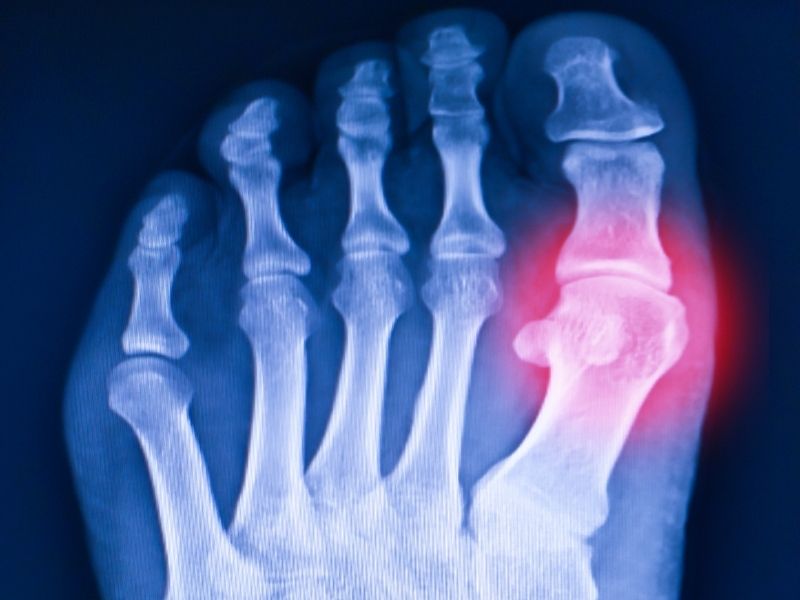

Eğer bu eklem sertleşirse, yürümek çok ağrılı ve zor hale gelir. Metatarsofalengeal eklem, her hangi bir eklemde olduğu gibi, düz bir eklem kıkırdağıyla örtülmüş kemiklerde sonlanır. Aşınma ve yırtılma olayı varsa veya eklem kıkırdağında hasar varsa, ağrılı kemik sonları birbirine sürter. Kemik çıkıntısı veya aşırı büyüme, kemiğin tepesinde gelişebilir. Bu aşırı büyüme, yürüdüğünüz zaman, parmağınızın ihtiyacı olduğu kadar bükülmesine mani olur. Sonuç; sert bir ayak baş parmağı veya hallux rigidusdur.

Doktorunuz, ayağınızı muayene edecek ve bir kemik çıkıntısının (mahmuzunun) kanıtını arayacaktır. Parmağınızı, etrafında döndürerek ne kadar hareketin ağrısız olabileceğini görecektir. Röntgen filmleri, herhangi bir kemik çıkıntısının büyüklüğünü ve yerleşimini gösterebileceği gibi, eklem aralığında ve kıkırdak dokusunda ne derecede bir dejenerasyon olduğunu da gösterecektir.